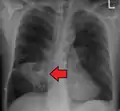

- تصوير الصدر بالأشعة السينية وأخرى

يُصيب الخراج في كثير من الأحيان جانب واحد ويشمل القطاع الخلفي من الفص العلوي والقطاعات القمية من الفص السفلي عند الإستلقاء. وجود بعض المستويات من هواء سائل يؤدي إلى تمزقات في القصبة أو في قليل من الأحيان نمو الغاز وبالتالي تكوين كائن حي.